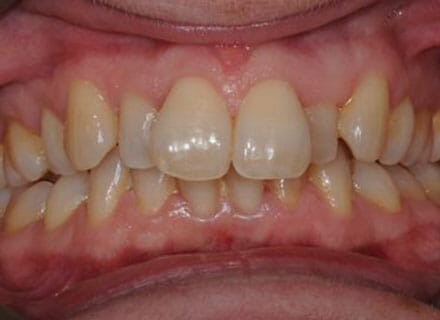

In this case, we needed to reduce the size of the central incisors as they were just too big. This combined with the crowding at the front had caused the lateral incisors to become trapped inside, pushing the big central incisor teeth forwards even more. After reducing the big teeth to a normal size we started with fixed clear bracket brace treatment and were able to complete this case in a little over a year.